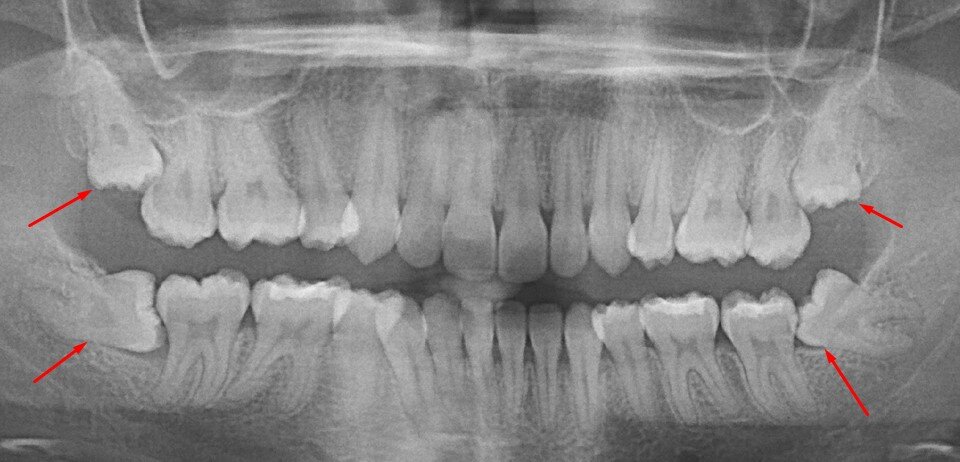

Это снова не так! Зубы мудрости могут расти косо, неправильно вылезать или оказывать давление на другие зубы, что может привести к различным стоматологическим проблемам. В некоторых случаях, рекомендуется удаление таких зубов, чтобы избежать возможных проблем.

Случаи, когда зубы мудрости могут оказать влияние на смещение других зубов, обычно связаны с особенностями анатомии каждого конкретного пациента. Например, если зубы мудрости занимают неправильное положение или имеют нехватку места для нормального выхода, они могут оказать давление на соседние зубы и вызвать их смещение. В таких случаях рекомендуется удаление зубов мудрости, чтобы предотвратить дальнейшее смещение остальных зубов.

Осложнения связаны с тем, что у зубов мудрости часто не хватает места для правильного выравнивания. В результате, они могут вырасти криво, неправильно вступать в контакт с соседними зубами или просто не полностью прорезаться. Это может вызывать боли, воспаление десен, раздражение слизистой оболочки и другие неприятные ощущения.